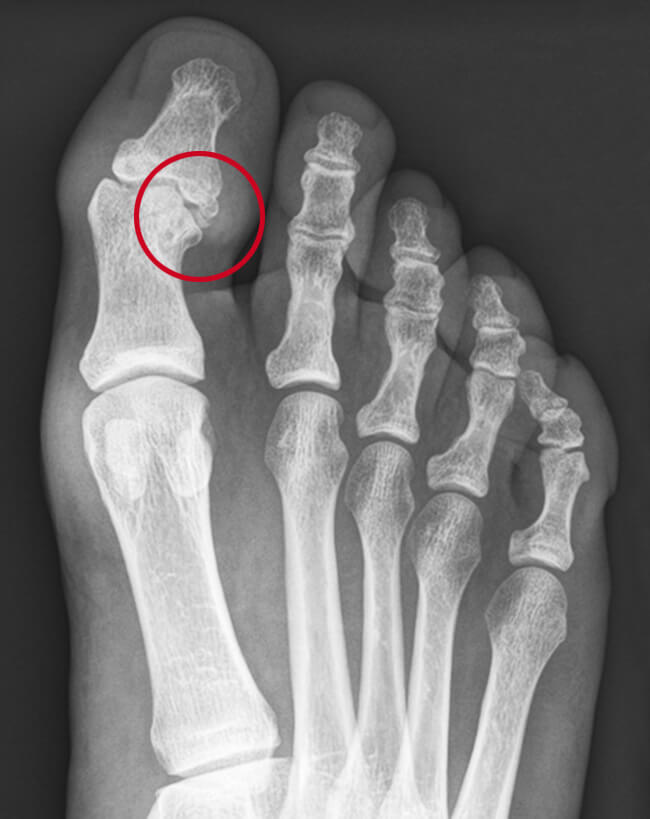

Artrose kan ontstaan door een ongeluk met de voet waarbij u bijvoorbeeld uw grote teen breekt. Als de breuk door het gewricht tussen de teenkootjes loopt, kan kraakbeenschade ontstaan. Of het teenkootje kan scheef komen te staan waardoor het kraakbeen extra snel slijt. Dit heet posttraumatische artrose en kan jaren na de breuk alsnog optreden.

In dit IP-gewricht ziet u aan de rechterzijde een oude vastgegroeide breuk waardoor het gewricht scheef is gaan staan. Er bevindt zich een klein stukje bot in het gewricht. Er heeft zich tevens aan de bovenzijde een bult op het gewricht gevormd.